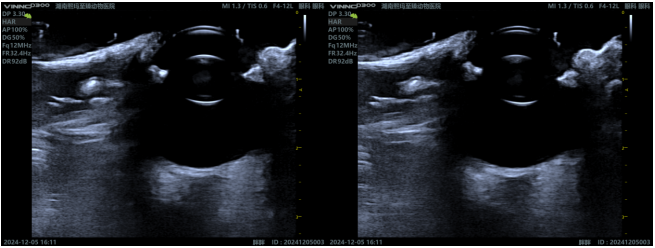

Ocular Ultrasound: